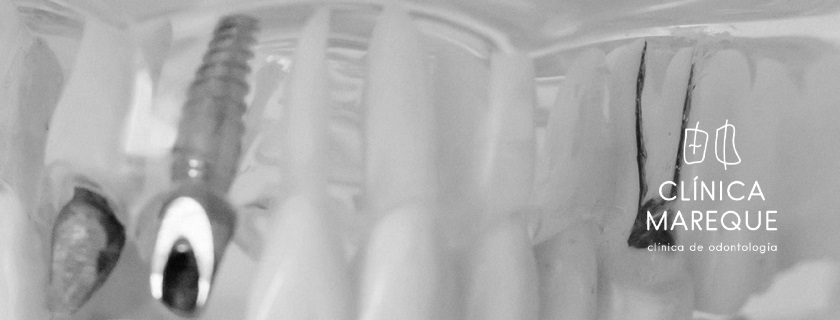

Los implantes dentales son raíces artificiales, generalmente de titanio, que se colocan en el hueso maxilar o mandibular para reemplazar dientes perdidos. Sobre ellos se fija una prótesis o corona que imita la apariencia y función de un diente natural.

Perfectos para sustituir un diente perdido con una corona individual sobre un solo implante.

Para restaurar varias piezas dentales, se colocan varios implantes que soportan un puente fijo.